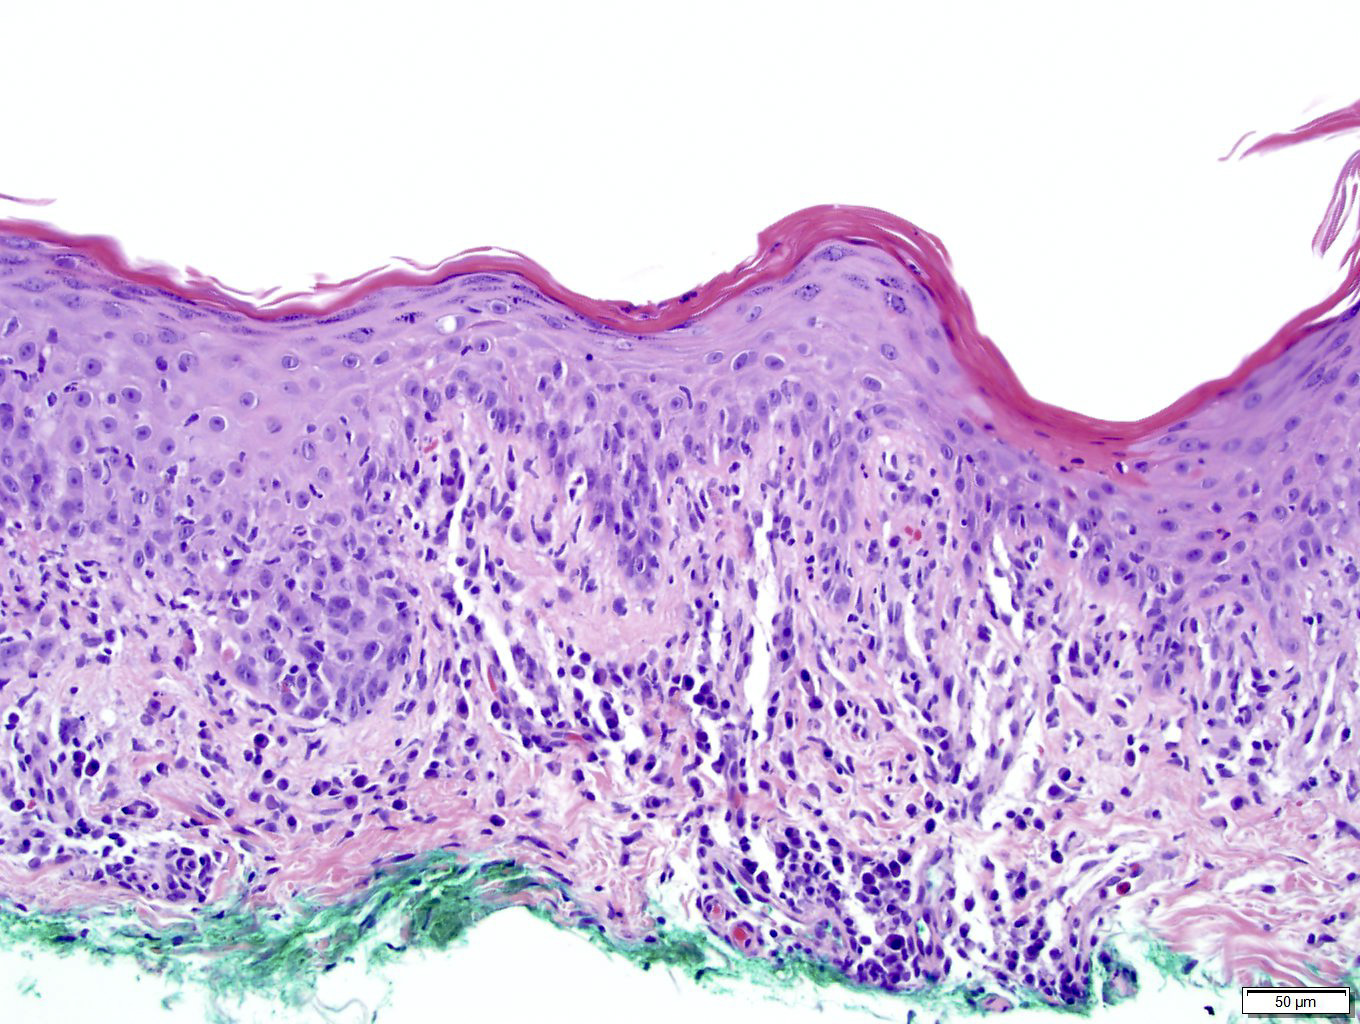

Microscopic (histologic) images

Contributed by Silvija P. Gottesman, M.D., Hillary Rose Elwood, M.D., Mark R. Wick, M.D. and AFIP images

Microscopic (histologic) description

- Primary syphilis: ulcer with lymphoplasmacytic inflammation

- Secondary syphilis:

- Lichenoid superficial and deep perivascular and periadnexal lymphohistiocytic inflammation with admixed plasma cells

- Plasma cells may be absent in 33% of biopsies

- Eosinophils can be present

- Marked endothelial swelling and proliferation of blood vessels can be seen

- Commonly identified are vacuolar interface change, acanthosis or lymphocyte exocytosis

- Skin, punch biopsy:

- Psoriasiform lymphohistiocytic inflammation with plasma cells (see comment)

- Comment: There is psoriasiform epidermal hyperplasia with superficial and deep perivascular lymphohistiocytic infiltrate. Admixed plasma cells are also noted. The infiltrate forms a band beneath the hyperplastic epidermis and envelopes some of the adnexal structures. Endothelial swelling of the superficial vascular plexus is present. A treponemal immunohistochemical stain shows numerous coiled spirochetes in the lower half of the epidermis. These findings are diagnostic of syphilis.